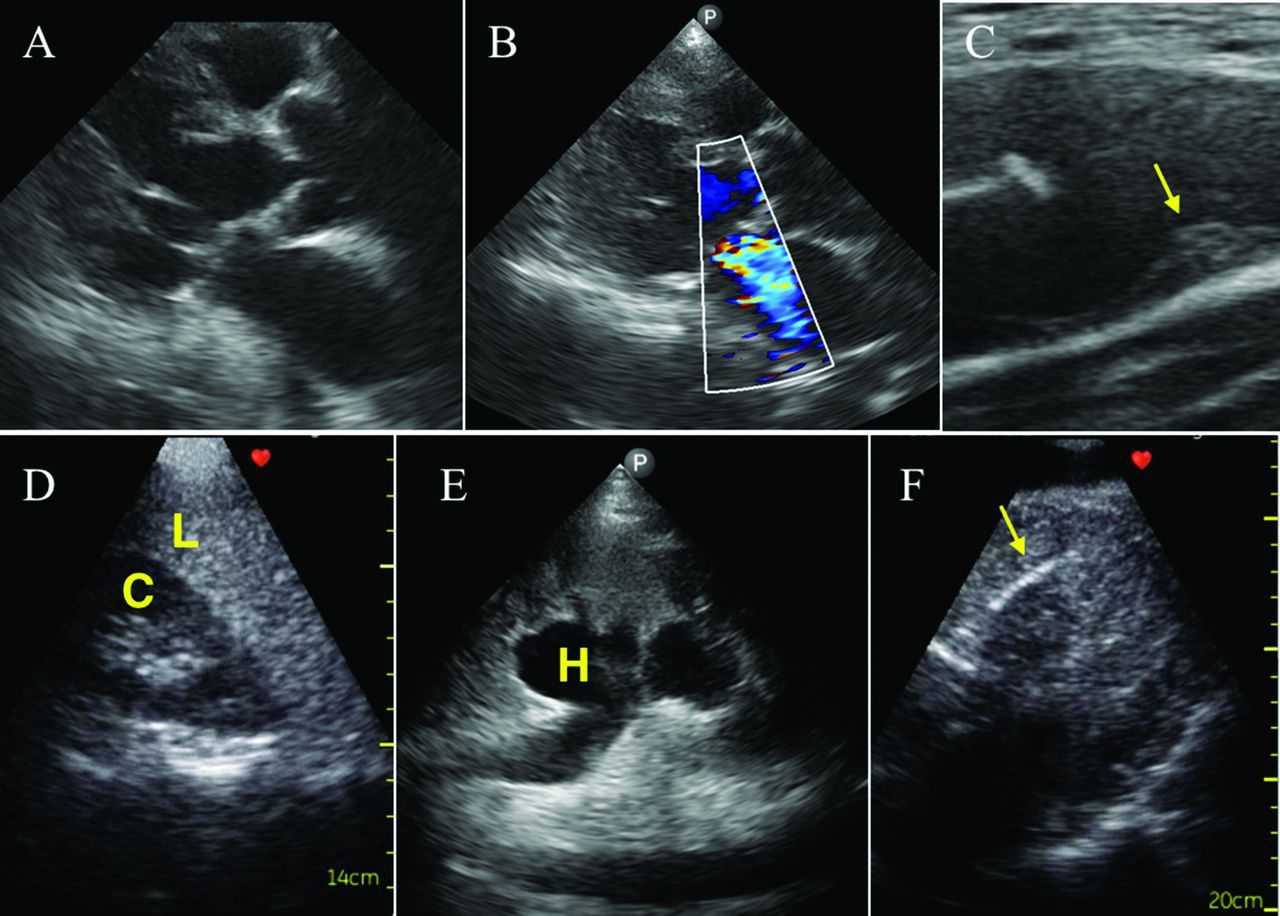

Ejemplos de usos y patologías detectadas por medio de ultrasonido.

• CARDIACO

CARDIACO

Desde valorar rápidamente la fracción de eyección y trastornos de motilidad, hasta ver la presencia de derrame pericárdico o valvulopatías.

• VCI y estado hemodinámico

VCI y estado hemodinámico

Se puede ver el estado de la vena cava superior y su relación con la fludoterapia del paciente para toma de decisiones de tratamiento.